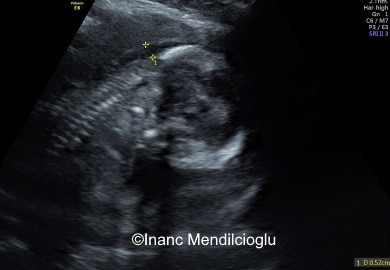

High thickness measurements are also associated with congenital heart defect . [1] The scan is carried out at 11-13 .6 weeks pregnancy and assesses the amount of fluid behind the neck of the fetus - also known as the nuchal fold or 'the nuchal translucency' . Fetuses at risk of Down tend to have a higher amount of fluid around the neck .

A nuchal scan or nuchal translucency (NT) scan/procedure is a sonographic prenatal screening scan to detect chromosomal abnormalities in a fetus, though altered extracellular matrix composition and limited lymphatic drainage can also be detected . . Since chromosomal abnormalities can result in impaired cardiovascular development, a nuchal translucency scan is used as a screening, rather than . . .

In the majority of fetuses with trisomy 21, the nuchal translucency thickness was <4 .5 mm, while with trisomies 13 or 18 it was 4 .5-8 .4 mm, and in those with Turner syndrome it was 8 .5 mm or more 9 . Correlation with serum markers

Figure 2 . Increased nuchal translucency thickness (NT) The findings of numerous studies suggest that an effective first trimester screening for trisomy 21 can be obtained by the combination of maternal age and measurement of fetal NT [4-11] .At a risk cut-off of 1 in100, the detection rate of trisomy 21 is about 75%, at a false positive rate of about 2% .

ultrasonography as increased nuchal translucency in the third month of intrauterine life . Fetal nuchal translucency thickness at the 11-13+6 weeks scan has been combined with maternal age to provide an effective method of screening for trisomy 21; for an invasive testing rate of 5%, about 75% of trisomic pregnancies can be identified .